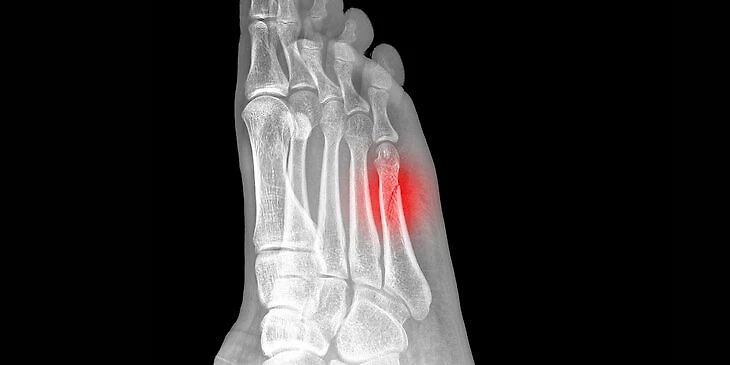

● А что такое стрессовый перелом? Это травма, которая появляется из-за множества микроповреждений – для нее не нужны сильный удар или разовая сверхнагрузка.

По сути, приземление с каждого прыжка или толчок зубцом конька об лед вызывают микроповреждения, которые не несут угрозы и быстро восстанавливаются сами по себе.

Но из-за регулярных нагрузок и недостатка отдыха такие повреждения не успевают залечиваться, а накапливаются, костная ткань изменяется. Особенно быстро это происходит в том случае, если спортсмен плохо питается и/или работает на серьезном дефиците калорий.

У детей такие травмы встречаются чаще, так как кости у них не такие плотные, как у взрослых.

Восстановление при стрессовых переломах занимает от четырех недель до полугода – все зависит от тяжести травмы. Но вернуться на прежний уровень реально.